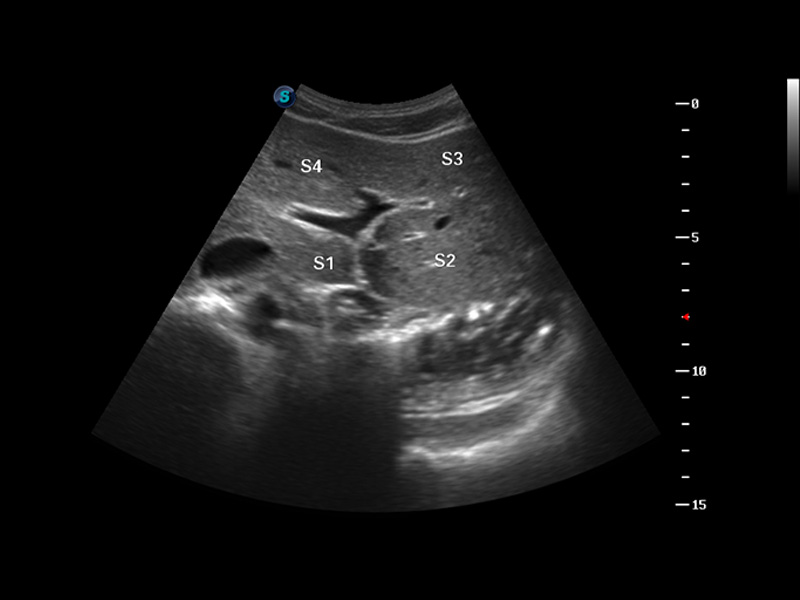

S8 EXP便携式彩色多普勒超声诊断仪是环球UG官网研发的高端全身应用型便携彩超。高通道的VIS平台融合可视化(Visual)、智能化(Intelligent)和人性化(Smart)的特点,配以环球UG官网自主研发生产的探头大家族,使您能够快速、准确的获得病人信息,提高工作效率的同时减轻疲劳。

成像技术

多波束形成器

μ-Scan微米成像

谐波成像

实时宽景成像

空间复合成像

3D/4D成像